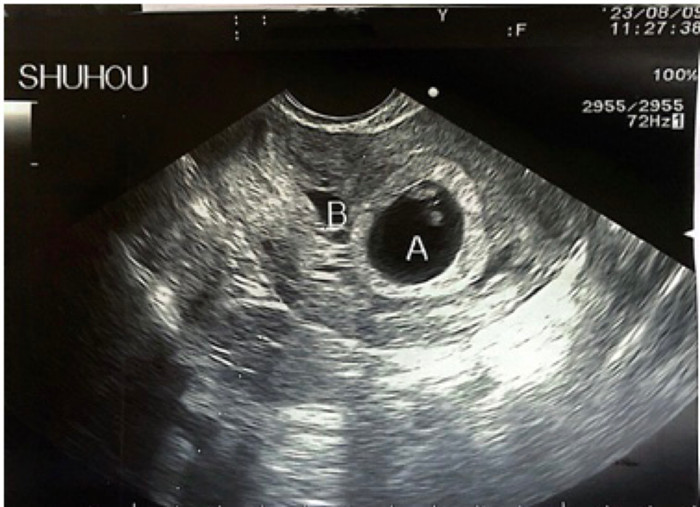

幸运的是,经过细致的超声评估梁女士子宫瘢痕处的肌层较厚、孕囊仅部分着床于此处,属于子宫瘢痕妊娠Ⅰ型,且宫内胎儿发育良好。在与梁女士夫妇充分沟通手术相关风险和并发症后,夫妻要求保留宫内胎儿意愿极为强烈。生殖中心医护团队为梁女士制定详细的手术方案,在做好备血、抢救准备后,于 8月9日在梁女士孕7周时,由经验丰富的刘风华主任医师为其进行阴道超声引导下胚胎减灭术,成功减灭子宫瘢痕处妊娠。术后住院安胎、观察,梁女士无腹痛、阴道流血的情况。术后一周复查超声,宫内胎儿发育良好。

手术后超声可见宫腔内正常妊娠的孕囊A和空虚的孕囊B